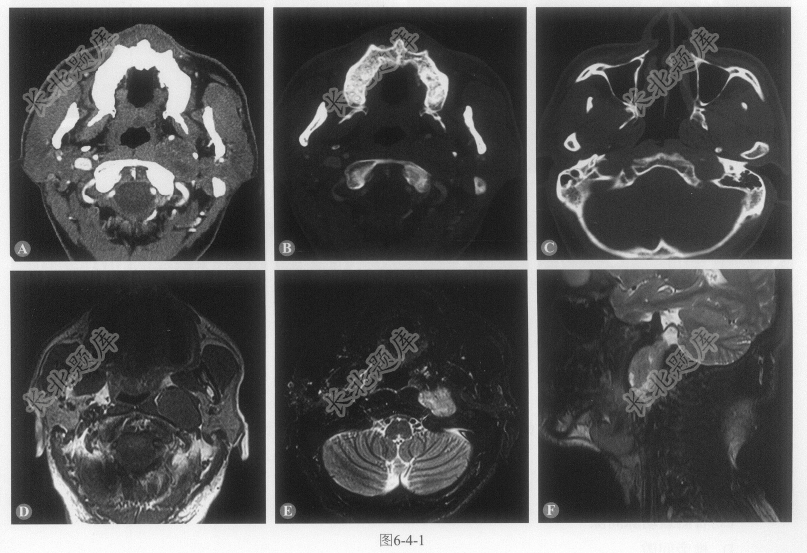

- 单项选择题患者男性,48岁,声音低沉4年,声嘶2年,加重伴呛咳2个月。CT、MRI图像如图6-4-1。下列说法错误的是:

A、左侧咽旁间隙(茎突前间隙)肿块,信号不均

B、左侧颈静脉孔增大

C、病灶与腮腺之间脂肪间隙存在

D、病灶小部分向上经颈静脉孔延伸至颅内

E、病灶邻近颈内动脉受压前移,颈静脉受压显示不清